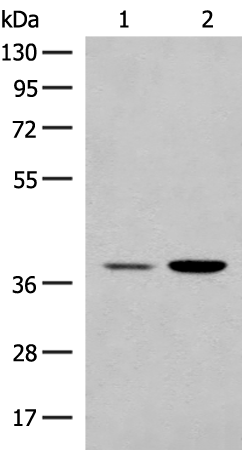

分类: 科研抗体货号: P02794别名:应用: WB,IHC反应种属: Human, Mouse, Rat